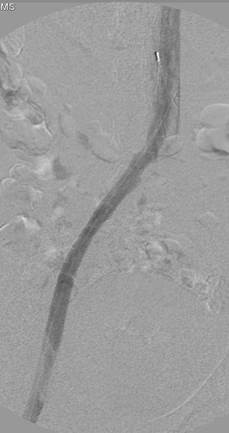

Eliminación razonable del trombo en las venas ilíacas tras una sola pasada del catéter DVX de AngioJet (25 mg de tPA en 250 cc de solución salina normal).

Venograma final tras la aspiración con catéter grande y tratamiento de la estenosis subyacente (debido a la compresión extrínseca del tumor) con un stent de 16 mm con el balón inflado a 12 mm.

Tiempo total: <90 minutos. Flujo interno perfecto de la parte posterior de la rodilla a la vena cava inferior (VCI).